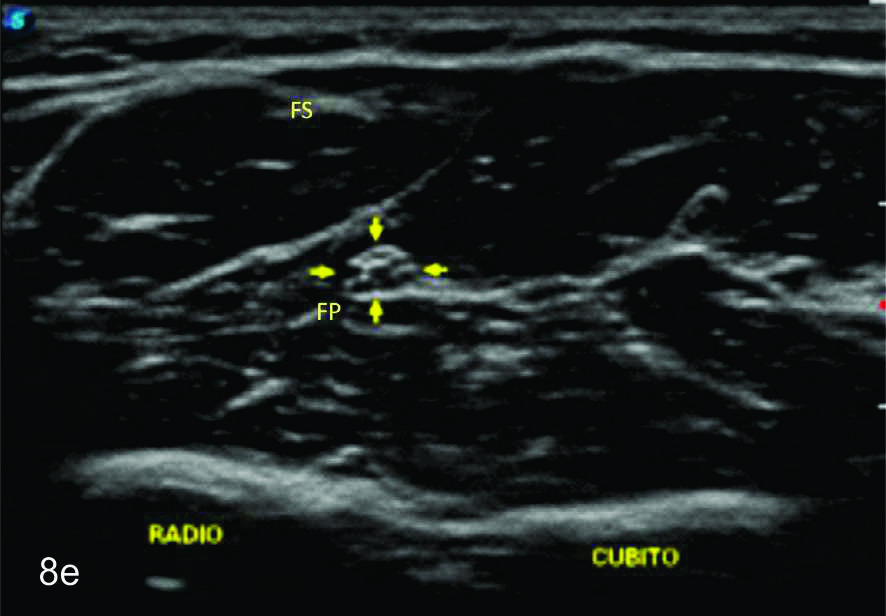

Figura 8

Nervio mediano

Serie de cortes axiales del nervio mediano desde su origen a nivel del hueco axilar hasta el sector distal del antebrazo previo a su ingreso al túnel del carpo. Se identifica el mismo señalado por flechas amarillas y con la palabra mediano. AA-arteria axilar, VA- vena axilar, AH- arteria humeral, VH- vena humeral, VB- vena basilar, AC- ateria cubital, VC- vena cubital, BA- músculo braquial anterior, PR- músculo pronador cuadrado, FS- músculo flexos superficial, FP- músculo flexor profundo, PC- músculo pronador cuadrado. A- axila, se identifica el nervio superfical a la arteria axilar, B- tercio medio del brazo en canal bicipital medial, lateral a la arteria humeral, C- codo, medial al tendón distal del bíceps braquial y a la arteria humeral luego de cruzarla, superficial al músculo braquial anterior, D-antebrazo sector cefálico, entre las dos cabezas del pronador redondo, E- tercio medio del antebrazo, entre los músculos flexor superficial y profundo F- tercio distal antebrazo, superficial al pronador cuadrado.